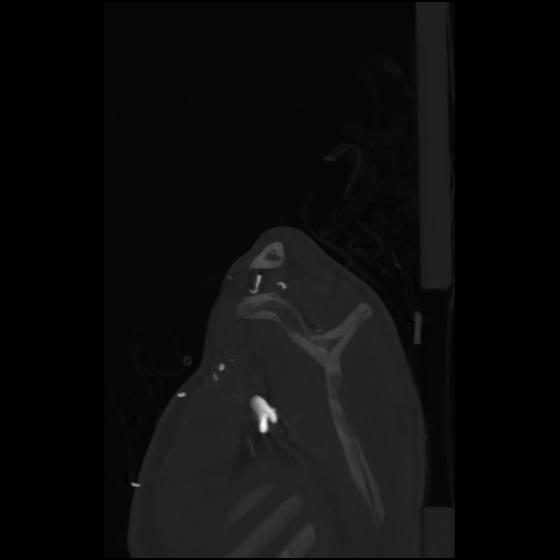

24 ANGIO,CE,Sag-MIP,5.000,ANGIO,Sag-MIP,